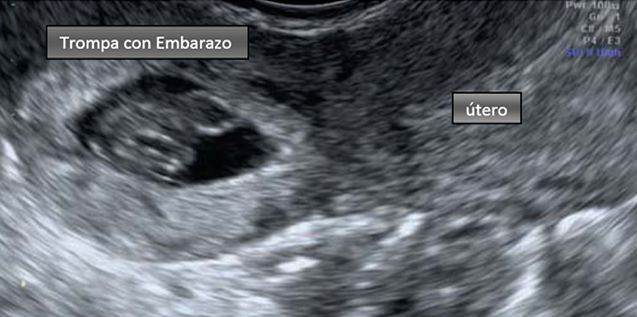

DIAGNÓSTICO CLÍNICO Retraso menstrual: Suele ser menor de 10 semanas Dolor abdominal: Dolor en bajo vientre o en una de las fosas iliacas, generalmente es continuo, de intensidad variable, puede acompañarse de tenesmo vesical y se exacerba con el examen ginecológico Sangrado genital: escaso, irregular, rojo oscuro EXAMEN GINECOLÓGICO Espéculo: sangrado endocavitario escaso y oscuro " en borra de café" Tacto: Utero aumentado de tamaño y reblandecido, tumoración anexial dolorosa, en forma de "salchicha" , poco móvil y separada del útero. en casos de amenorrea menor de 6 semanas, no suele revelarse signos de embarazo, pero la movilización uterina suele ser molesta, se palpa una masa anexial dolorosa y poco móvil Dolor a la palpación del fondo de saco posterior. Signo de Proust LABORATORIO Determinación cuantitativa de la sub-unidad B coriónica ( se encuentra disminuida según laedad gestacional) Progesterona, valores mayores de 25 mg/ml sugiere embarazo anormal como lo es el embarazo ectópico ECO tranvaginal: con criterio de diagnóstico que son: 1. Útero vacío, 2.masa anexial heterogénea, 3. Saco extrauterino con halo hipercogénico alrrededor, 4. Saco con vesicula vitelina o botón embrionario con o sin actividad cardíaca extrauterina Culdocentecis positiva: es la presencia de sangre no cuagulable en el fondo de saco de Douglas Biopsia endometrial: reacción residual si vellosidad corial NOTA: el diagnóstico definitivo del embarazo ectópico no complicado se hace por laparoscopia